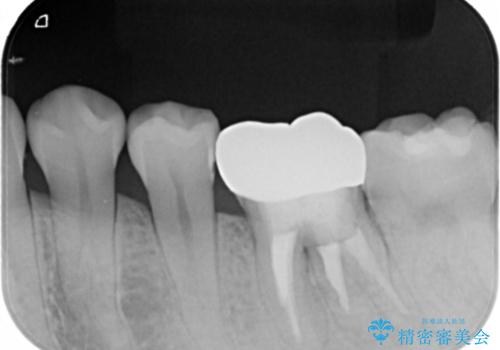

既に治療されている歯でしたが根尖部に病巣が確認出来たので、精密根管治療とクラウンの再治療が必要と判断されました。

精密根管治療を行なったことで病巣は消失し、腫れや痛みは再発することなく経過は良好です。

被せ物はフルジルコニアクラウンを選択されました。